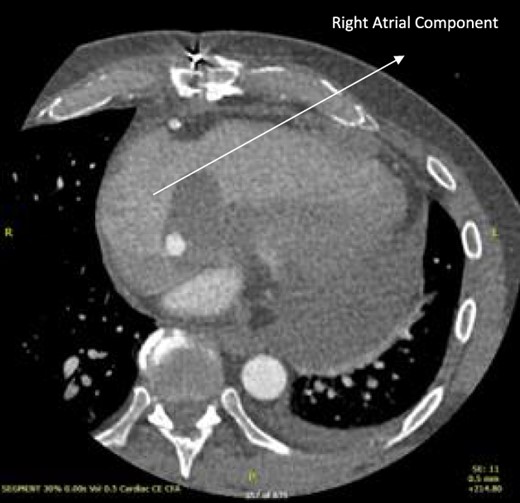

Follow-up CT scans were undertaken during chemotherapy that showed continued reduction in the size of the RA tumour, as demonstrated in Figs 4 and 5. The pericardial mass following chemotherapy is visualized in Fig. 6.

Post-operative CT scan during chemotherapy showing reduction of size RA bulk.